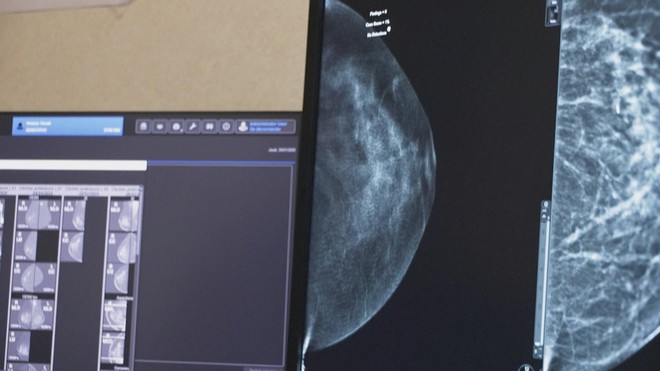

Nghiên cứu đã phân tích gần 106.000 ca chụp X-quang tuyến vú trong chương trình sàng lọc ung thư vú quốc gia Thụy Điển cách đây gần 5 năm. Trong đó, một nửa số ca được hai bác sĩ X-quang đọc độc lập theo quy trình thông thường, trong khi một nửa còn lại do một bác sĩ thực hiện với sự hỗ trợ của A.I..

Kết quả cho thấy việc sử dụng A.I. trong sàng lọc không chỉ giúp giảm khối lượng công việc liên quan đến đọc và phân tích hình ảnh, mà còn mang lại hiệu quả phát hiện cao hơn một cách nhất quán. Cụ thể, phương pháp có hỗ trợ A.I. phát hiện được 81% trường hợp ung thư, so với 74% khi không sử dụng A.I., mà không làm gia tăng tỷ lệ dương tính giả.

Nhóm nghiên cứu nhận định, nếu được triển khai rộng rãi, công nghệ này có thể hỗ trợ bác sĩ X-quang phát hiện ung thư vú ở giai đoạn sớm hơn, đồng thời giảm áp lực trong bối cảnh nhu cầu sàng lọc ngày càng tăng.